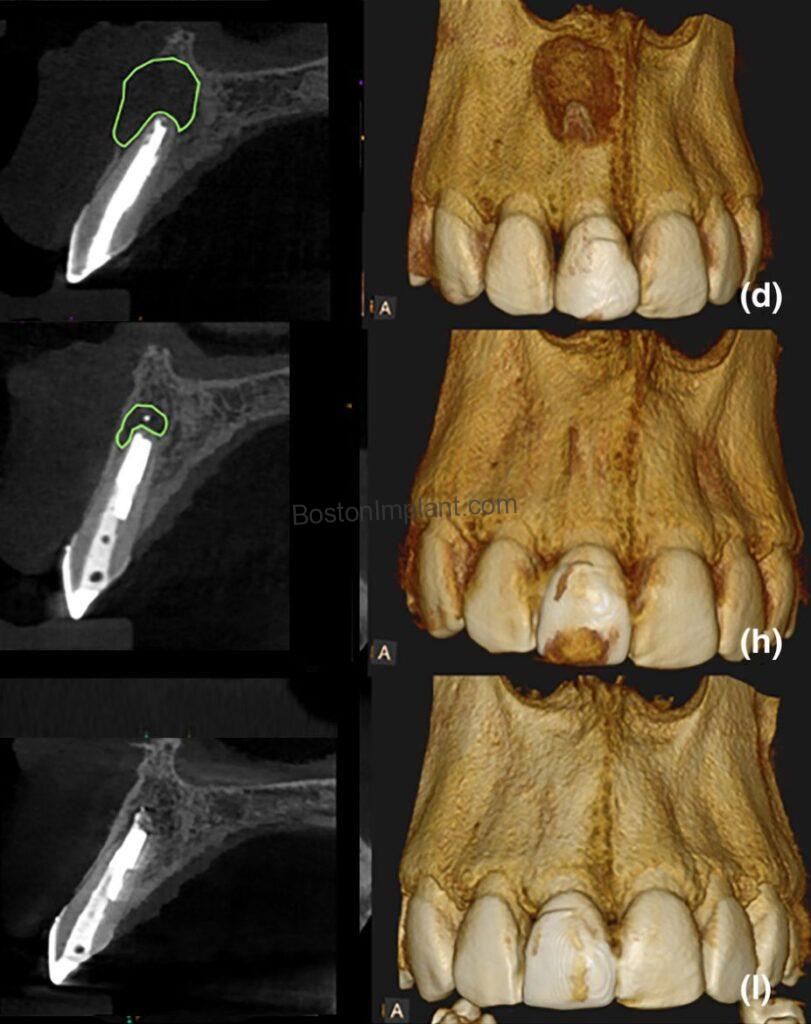

2. Endodontics (Root Canal Treatment): CBCT allows for a more thorough evaluation of endodontic issues, such as periapical lesions, which are difficult to assess with regular X-rays. It also helps us evaluate healing after successful root canal treatment.*